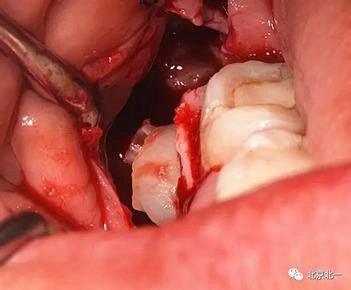

圖五:臨床所見

圖六:切開翻瓣, 看見骨面清晰,未見智齒